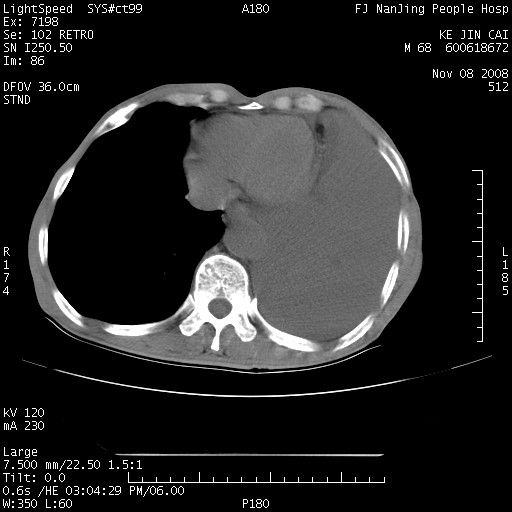

是个很有看头的病例,咋人气那么不旺?没多少人兴趣呢?这个病例几大怪:1   恶性肿瘤侵犯心肌左房怪,心肌一般不会被恶性肿瘤侵犯吧?2   左下肺均匀实变怪,内无含气,有别一般不张实变,含气肺泡完全为液体取代,而非一般不张实变的肺萎陷,冷不丁还以为是肿大的脾脏3   肿瘤本身怪,像tb肺不张4   这么有看头的病例没人气怪。呵呵。

左肺恶性肿瘤侵犯肺动脉,左心房内瘤栓,胸膜转移。

左肺恶性肿瘤侵犯肺动脉,左心房内瘤栓,胸膜转移,少见,学习了。